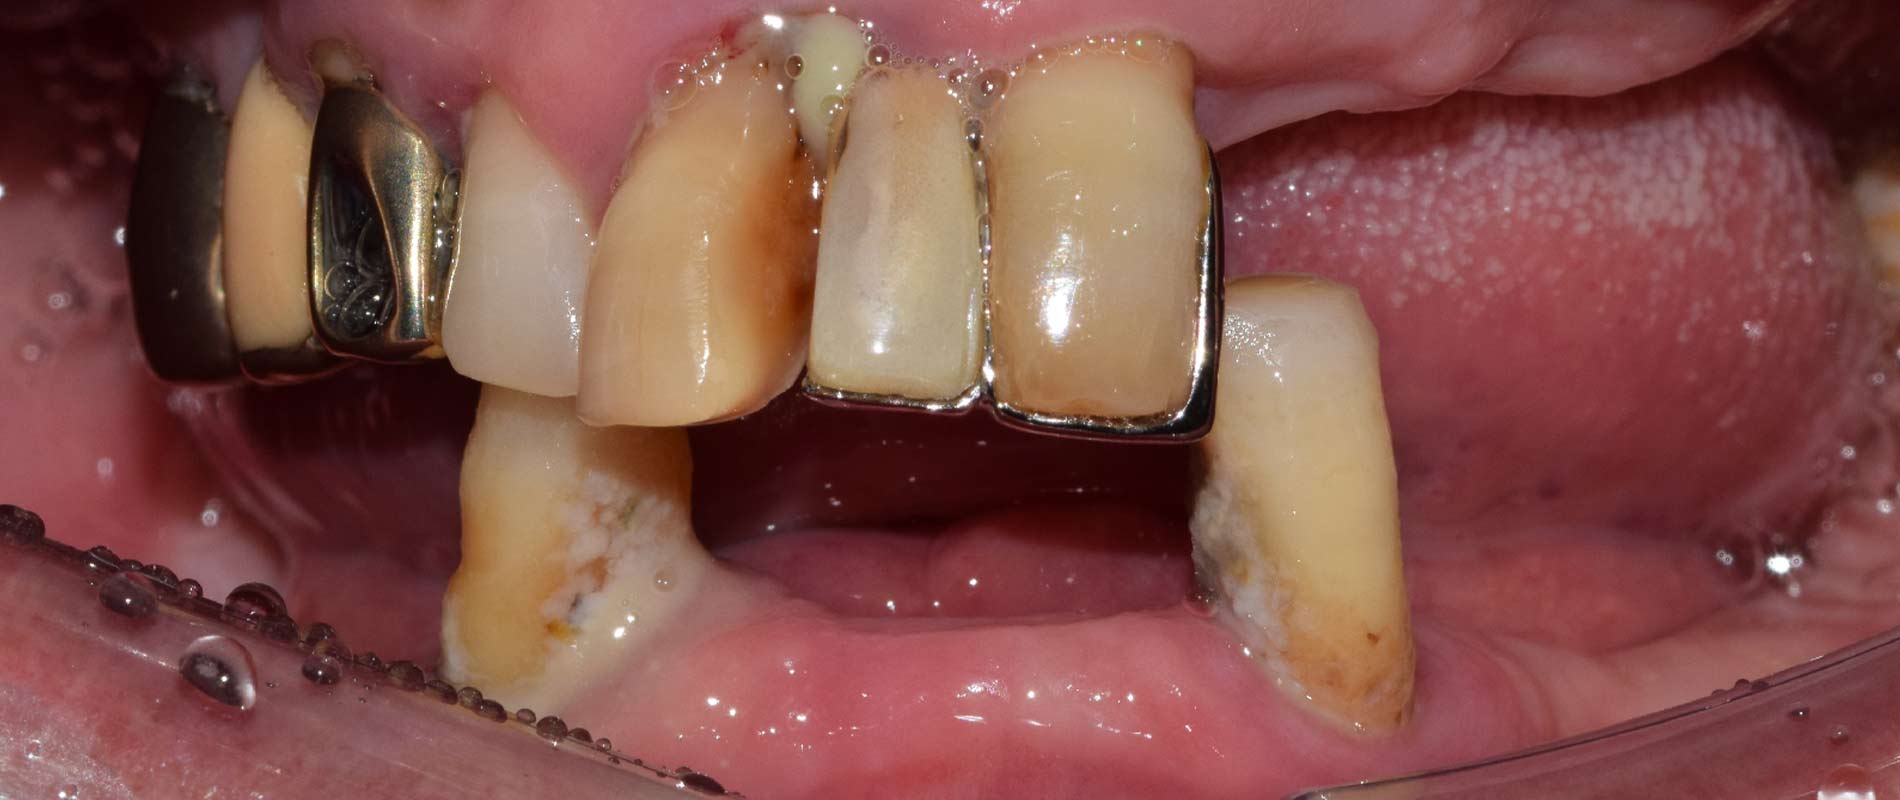

전후 수술 예시 사례

드림연합치과는 환자 중심 자연치아의 보존을 최우선으로 하며, 임플란트는 신중히 고려된 대안으로만 제안됩니다.

그러나 일상생활이 어려운 환자들을 위해, 풍부한 대학 병원 임상경험을 바탕으로 양한 임플란트 케이스에 대한 경험을 보유하고 있습니다.

우리의 목표는 단순한 치아 대체가 아닌, 환자의 삶의 질 향상입니다.

전체 임플란트 전 후 실제 사례

전체 임플란트 환자 사례 #1

🦷 전체 임플란트 수술 전 후 Case 1

🦷 전체 임플란트 수술 전 후 Case 2